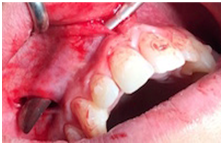

A 24 years old male presented with a bilateral molar class I malocclusion, severe crowding, open bite and reduced upper arch width (Figure 1). In order to avoid the palatal surgical expansion and considering the conclusions by Bhattacharya et al. according to which alveolar corticotomies not only can accelerate the orthodontic treatment but also provide the advantage of increased alveolar width to support the teeth and overlying structures, corticotomies were selected to assist the Invisalign® (Align Technology, San José, CA, USA) orthodontic treatment.4 A cone beam computed tomography (CBCT) scan was collected among all the conventional orthodontic and surgical diagnostic data in order to design the surgical assisted orthodontic treatment plan. CBCT data were very helpful in reviewing the orthodontic treatment plan via the Clin Check® planning in order to obtain a maxillary arch expansion of about 4mm in the premolar region with staging set at 0.25 mm per aligner. A total duration of 30months of treatment was forecasted. The patient did not report any systemic contraindication to surgery and provided written informed consent to the described procedures. All the statements of the Declaration of Helsinki were followed. The day when surgery was scheduled, the patient performed mouth-rinse containing 0.2% chlorhexidine for 1 minute pre-operatively and Mepivacaine (carbocaine 2% AstraZeneca S.p.a. Milan, Italy) with adrenaline 1:100.000 was infiltrated tea reducing bleeding at the surgical site. Full-thickness vertical gingival incisions were performed along the median and both in lateral frenula using a number 15 blade and not extending to the keratinized gingiva. Full thickness incisions were made cutting the mucosa to the periosteum, allowing the blade to touch the alveolar bone. A sharp periosteal elevator allowed wide subperiosteal tunneled dissection over the roots of the involved teeth, both mesially and distally (Figure 2) Subsequently, a piezoelectric micro saw (Surgysonic Moto® Esacrom S.r.l. Imola, Italy) was introduced into the tunnel created underneath the flap and interproximal corticotomies extended through the entire thickness of the cortical layer, just barely penetrating the medullary bone were performed between the dental roots following the long axis of the alveolus and stopping at a distance of 2 mm from the papilla up to the vestibular fornix, 4-5 mm above the apex of the teeth, not penetrating the maxillary sinus. Endoscopic assistance through fiber optic was not necessary because of the direct sight allowed by the frenula incisions. An established augmentation procedure was performed in this case. The suture of the vertical incisions using PGA 3–0 thread (Omnia S.p.a, Fidenza, Italy) in the muscular layer and Silk 3-0 thread (Ethicon, Johnson & Johnson, Somerville, NJ, USA) on the mucosa complete the surgical procedure. Prophylactic amoxicillin 2 gr per day medication was prescribed for one week; pain killing was achieved using Paracetamol 500mg+Codeine 30mg three times a day restricted to the first postoperative days to avoid interference with the RAP. Orthodontic treatment was resumed on the same day using Invisalign® aligners. During the RAP phase aligners were changed every 5 days, reducing of about one third the normal protocol of aligners changing (14 days).

Figure 2 The minimally invasive surgical access.